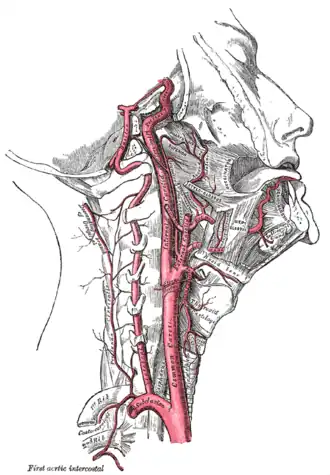

| The neck contains several vulnerable targets for compression, including the carotid arteries and the trachea. | |